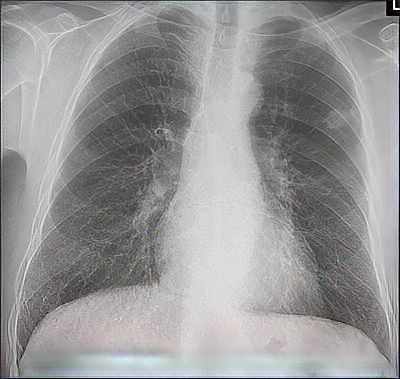

Röntgenbild einer Lunge

(Foto: de.wikipedia.org)

Nach dem letzten Krieg tauchte in Altrip verstärkt eine weitere Infektionskrankheit auf: die Lungentuberkulose. Vielleicht war dies mit ein Grund dafür, dass Altrip als Pilotprojekt für ein transportables Röntgengerät ausgewählt wurde. Ende Juli 1951 erhielt Bürgermeister Adam Jacob die Mitteilung, dass schon im August das Modellvorhaben gestartet werde. Diese „Schirmbild-Aktion“ war ein völlig neues Verfahren für eine kostengünstige Röntgen-Reihenuntersuchung des Thorax.

Auf einem Lastwagen wurde das Gerät nach Altrip befördert, wo seine Einzelteile von Technikern in einer Dreiviertelstunde zusammengebaut wurden. Ziel war die Erfassung der potenziell betroffenen Bevölkerung. Von der Technik her war es eine „normale“ Durchleuchtung, bei der der Patient zwischen der Röntgenröhre und dem Schirm stand.

Nachdem der Arzt der Tbc mit „Horchgeräten“ nicht auf die Spur kommen konnte („Tuberkulose wird nicht gehört; sie ist nur zu sehen!“), entwickelten amerikanische und deutsche Forscher entsprechende Röntgenapparate, die nach dem Krieg vervollkommnet wurden. Als erste Städte in der Pfalz schafften sich Kaiserslautern und Ludwigshafen solche Röntgengeräte an. Neben Schulkindern, Lehrern und Angehörigen Tbc-gefährdeter Berufe wurden im Gesundheitsamt Ludwigshafen auch allwöchentlich die Eheanwärter „beäugt“, insbesondere solche, die familiär vorbelastet waren.

Die heute 78-jährige Erna Wüst erinnert sich noch genau, dass sie damals als Kanzleiangestellte für das Standesamt stets Anfragen beim Gesundheitsamt starten musste. Mit dem in Altrip eingesetzten Schirmbildgerät wurden binnen weniger Tage über 1370 Männer und Frauen erfasst. Die Auswertung selbst erfolgte anschließend im Gesundheitsamt. Die staatliche Tuberkulosefürsorge war mit dem Gesamtergebnis „sehr zufrieden“.